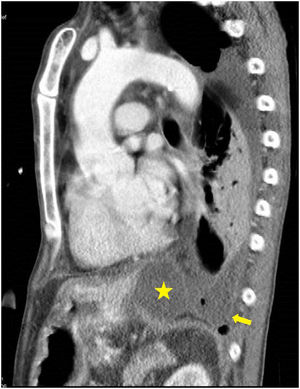

Fue llevado a urgencias de un centro hospitalario por el servicio de emergencias extra-hospitalario en situación de insuficiencia respiratoria hipoxémica grave y obnubilación concomitante. En la radiografía de tórax se apreció un patrón alvéolo intersticial en todo el campo pulmonar derecho y pulmón blanco izquierdo, con desviación de la tráquea hacia la derecha, sugestivo de derrame pleural masivo. Se realizó intubación orotraqueal, tras la cual se colocó un drenaje pleural izquierdo. El paciente persistió con insuficiencia respiratoria grave, apreciándose un patrón alvéolo intersticial bilateral con una imagen de neumotórax izquierdo. Este último, probablemente en relación con la poca distensibilidad pulmonar y la ventilación mecánica. Tras ello se procedió a colocación de otro drenaje pleural izquierdo sin obtener mejoría. Se derivó al paciente a nuestro centro. La bioquímica del líquido pleural fue: glucosa 181mg/dl, proteína de 3g/dl, LDH 528UI/l y amilasa 14.106UI/l. Los resultados microbiológicos de los cultivos (líquido pleural, aspirado traqueal, sangre, orina) fueron negativos. Tras estos resultados, se planteó la posibilidad de FPT. No se observó signos de insuficiencia cardiaca, y la ecocardiografía no apreció alteraciones; así mismo, no presentó afectación de otros órganos, ni respuesta inflamatoria sistémica. Se colocó un tercer drenaje pleural con cierta reducción del neumotórax. Tras ello, el paciente presentó mejoría progresiva, con desaparición del infiltrado alvéolo-intersticial y fue destetado de la ventilación mecánica tras 9 días de estancia en medicina intensiva. Tras ello, se realizó una tomografía computarizada de tórax y abdomen en la que se demostró la FPT (figs. 1 y 2). Posteriormente, el paciente pudo ser dado de alta a domicilio.

La FPT es causada por una disrupción del conducto pancreático, que conduce a la salida de secreciones pancreáticas al tórax, a través del hiato aórtico o esofágico1, provocando un seudoquiste mediastínico2,3, una fístula pancreático-bronquial, una fístula pancreático-pericardial4 o una fístula pancreático-pleural5. La mayoría de los casos de FPT son causados por pancreatitis crónicas. El caso descrito se trata de una fístula pancreático-pleural. Para el diagnóstico se utiliza la tomografía computarizada6, la resonancia magnética, la colangiopancreatografía por resonancia magnética y la colangiopancreatografía endoscópica retrógrada. Siendo estas 2 últimas más precisas para localizar el lugar de disrupción. El abordaje terapéutico, además de la suspensión de la dieta enteral y la administración de somatostatina o octreotide, incluye la colocación de un stent pancreático por vía endoscópica o mediante sutura de la disrupción en cirugía abierta y, por último, el tratamiento conservador7. Este último fue el tratamiento que se utilizó en nuestro caso, con resultado clínico favorable, y que consistió fundamentalmente en drenar el líquido pleural. Decidimos el tratamiento conservador por la buena respuesta inicial que presentó en nuestro centro, tras la colocación del último drenaje pleural. Esa también fue la razón por la que no solicitamos una colangiopancreatografía por resonancia magnética durante su estancia en el servicio de medicina intensiva.